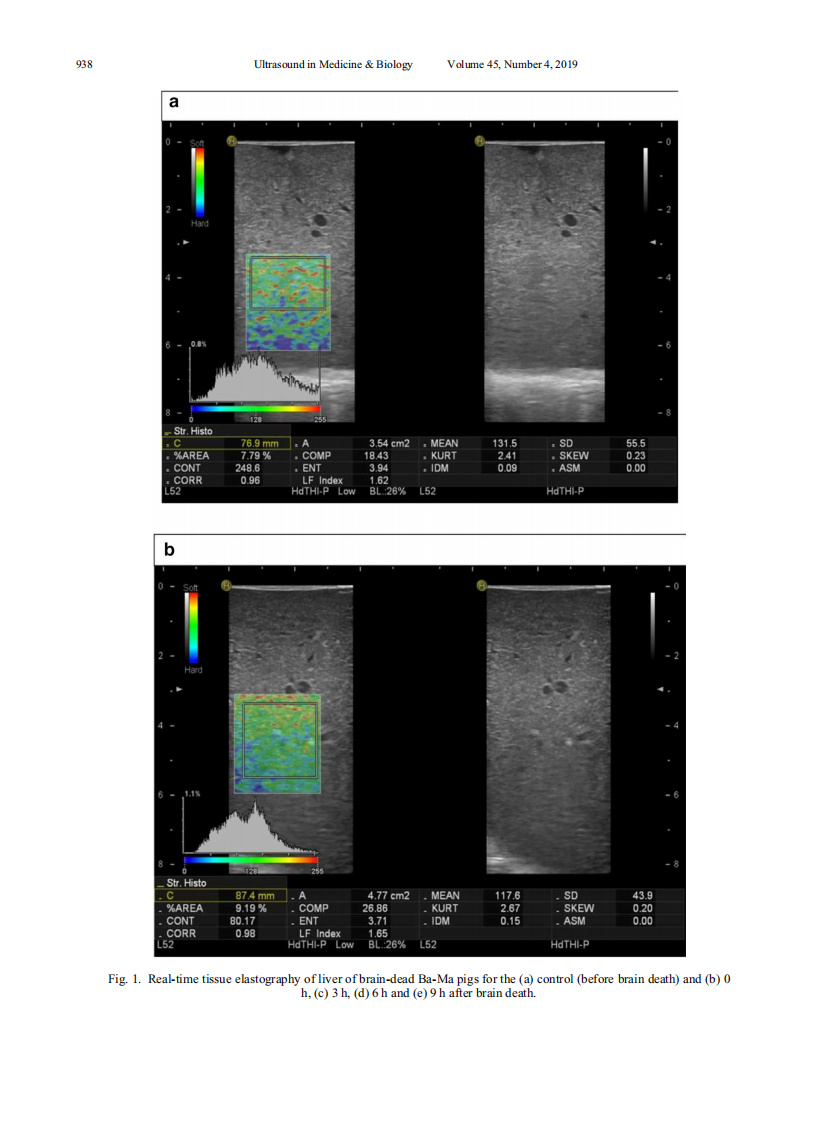

3)A comparison study of RTE and electron microscopy for assessment of liver damage.pdf

8)超声多模态评价猪脑死亡状态下肝脏损伤的实验研究.pdf